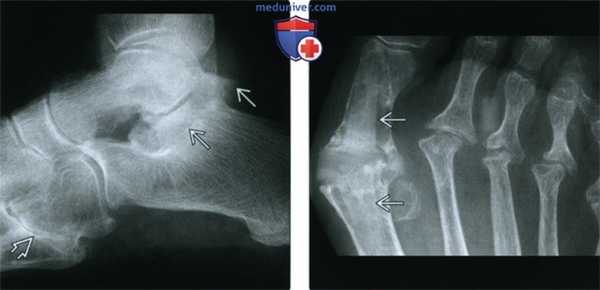

(Слева) Рентгенография в боковой проекции: эрозия заднего отдела пяточного бугра. Это не специфический признак воспалительной артропатии; РА может быть таким же вероятным диагнозом, как псориатический или хронический реактивный артрит.

(Справа) Рентгенография в ПЗ проекции: значительно выраженное эрозивное поражение 2-5 плюснефаланговых суставов, а также 1 -го межфалангового сустава у этого же пациента. Здесь отсутствуют признаки периостита, которые позволили бы предположить наличие псориатического или хронического реактивного артрита. Области поражения характерны для РА и подтверждают диагноз.

(Слева) Рентгенография в боковой проекции: типичное для РА эрозивное поражение среднею отдела стопы. Также обратите внимание на склерозированный линейный выступ пяточной кости. Этот и другие патологические переломы у этого пациента легко не заметить.

(Справа) Рентгенография в ПЗ проекции: результат резекции головок 2-4 плюсневых костей-распространенного варианта лечения болезненных деформаций плюснефаланговых суставов у пациентов с РА. Пациенту была выполнена артропластика 1-го плюснефалангового сустава эндопротезом Swanson, которая закончилась несостоятельностью конструкции и массивным остеолизисом.